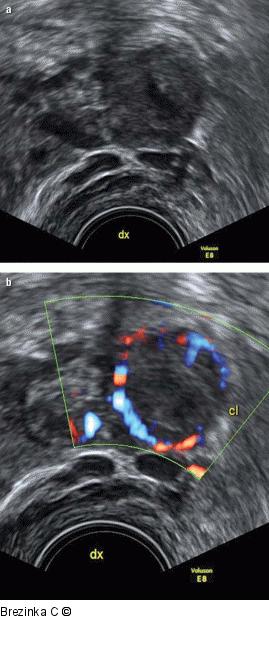

Abbildung 1a-b: Gyn-Ultraschall Ein unspektakuläres Corpus luteum (a) wird durch den „ring of fire“ im Farbdoppler zu einer markanten Struktur und einer einfachen Diagnose (b). |

Ein unspektakuläres Corpus luteum (a) wird durch den „ring of fire“ im Farbdoppler zu einer markanten Struktur und einer einfachen Diagnose (b). |